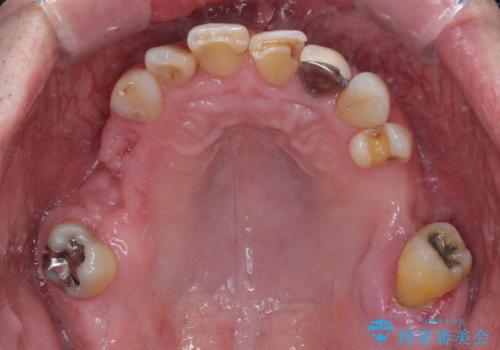

右下は奥歯が抜歯したスペースを塞いでしまい、左下はブリッジの支台歯の1つが破折している状態でした。

また、下顎前歯にはスペースがあり、コンポジットレジンでスペースを閉じている状態だったので、前歯のスペースを解消しつつ、奥歯にスペースを獲得するよう矯正治療を行うこととしました。

並行して左下にはインプラントを埋入し、上顎臼歯部の気になる部分も根管治療などを進めて行き、矯正治療を終えると同時に補綴治療を行うこととしました。